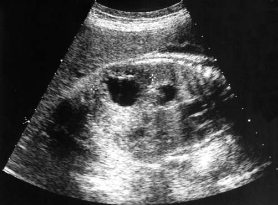

This sonogram of an early second-trimester cranium is most suspicious for:

holoprosencephaly